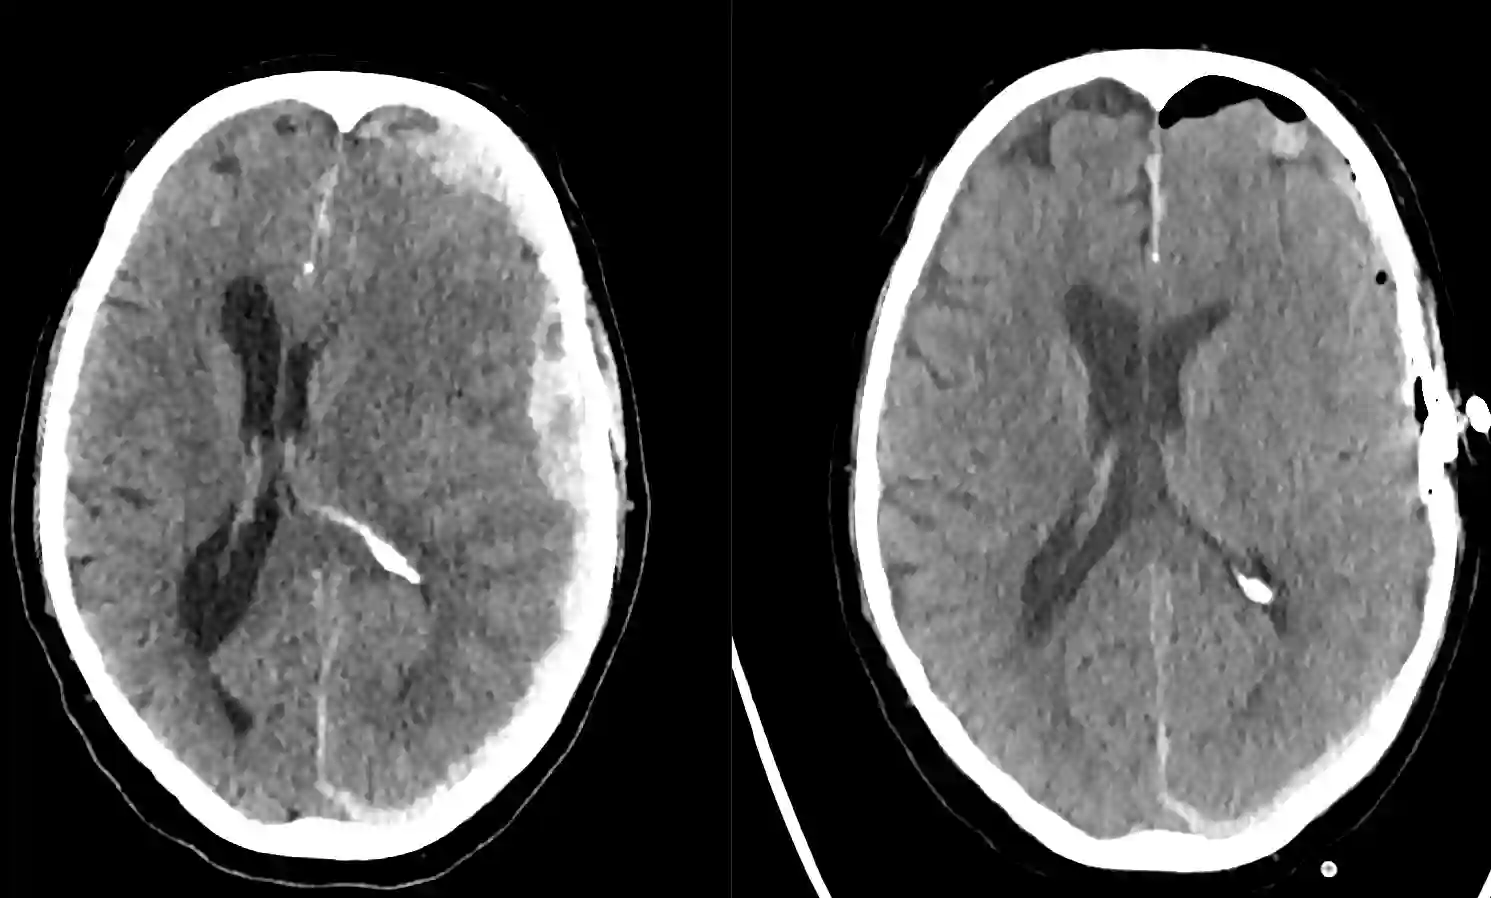

Akutes Subduralhämatom im CT

Ein akutes rechtsseitiges Subduralhämatom im Schädel CT.

Hyperakutes Subduralhämatom

Traumatische hyperaktus Subduralhämatom rechtsseitig im CT.

Akutes Subduralhämatom vor und nach Operation

Axiales CT Bild eines akuten Subduralhämatoms auf der linken Seite. Links vor der Operation und rechts nach durchgeführter Kraniotomie und Hämatomentlastung.